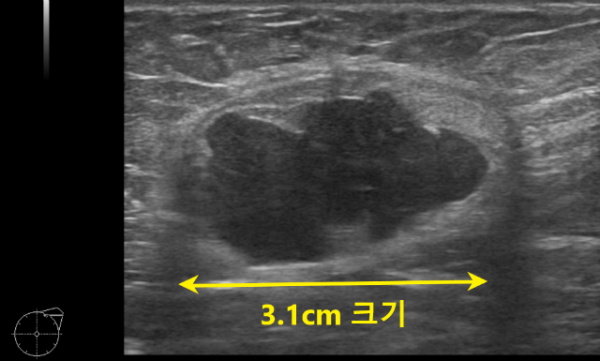

진찰상 왼쪽 겨드랑이에 대략 3cm 크기의 단단한 멍울이 만져졌고 임파선이 커졌을 가능성도 있었지만 멍울 이외에 겨드랑이에 부유방도 있었기 때문에 부유방에 생긴 결절의 가능성도 생각했었습니다.

다른병원에서 시행한 유방 촬영 사진을 가져오시지 않아 바로 유방 초음파 검사를 시행하였습니다.

모양으로 보았을때 림프절 비대 소견은 아니었으며 예상했던 대로 부유방안에 생긴 병변으로 판단되었습니다.

혹의 크기와 모양으로 보았을때 악성의 가능성이 높아보여 환자분께 설명드린후 바로 총생검검사를 진행하였습니다.